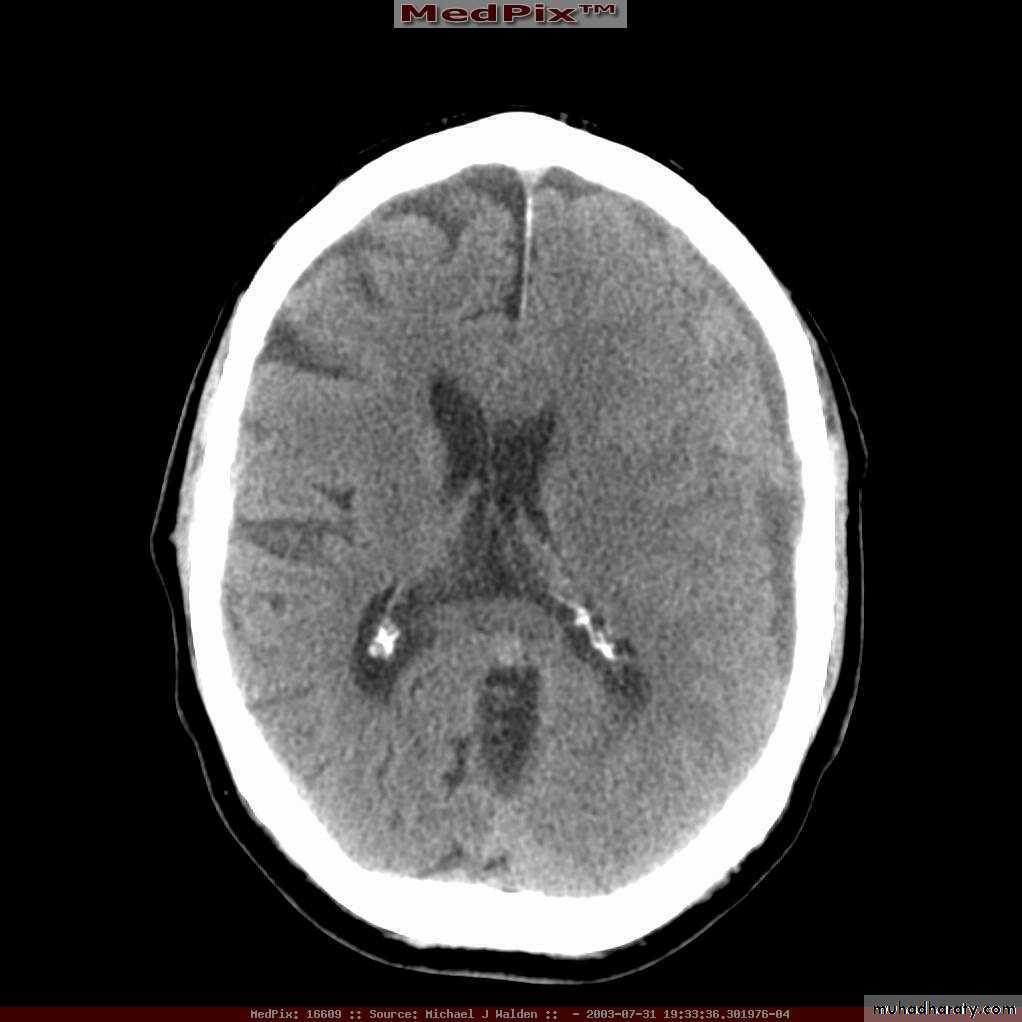

D. Intraventricular Hemorrhage:

• Blood filling ventricle (usually due to a blunt injury).• Treatment is conservative.